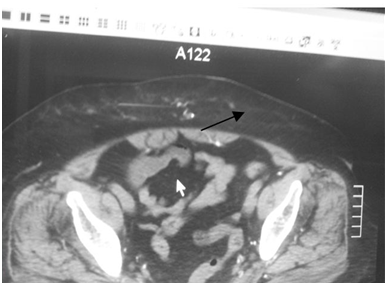

A 74 years old lady known to have end stage renal disease secondary to long standing diabetic & hypertensive nephropathy has been on hemodialysis since November 2010. Hypothyroidism on Eltroxin 150ug, hyperlipidemia on atorvastatin was admitted to the surgical department for debridement of her painful lower abdominal skin lesions which were progressing in size x 3weeks. No history of recent contrast exposure, trauma or any local injections other system review was irrelevant. On examinations there were skin lesions (Figure 1) in the form of ill-defined black indurated tender plaques, varying in size, scattered only in her lower abdominal wall with no observed lymphadenopathy or discharge. Rest of her general and local examination was unremarkable. Her laboratory investigations showed: Serum creatinine 855umol/l, BUN 19umol/l, S-albumin/total proteins 27/55, CK Normal. Serum calcium 2.5umol/l. S-phosphorus 1.5 umol/l, Ca x ph 3.75. PTH range over last 6 months was around (I molecule 13.5 -21pmol/l. Wbc’s 10.Hgb 8.9 platelet 175. ECG , ECHO & Nuclear study all were normal, Parathyroid U/S and scan were normal. CT scan (Figure 2) showed subcutaneous calcifications, skin biopsy (Figure 3) shows intramural calcific deposits.

Figure 2 Sub cutaneous calcification (black arrow).